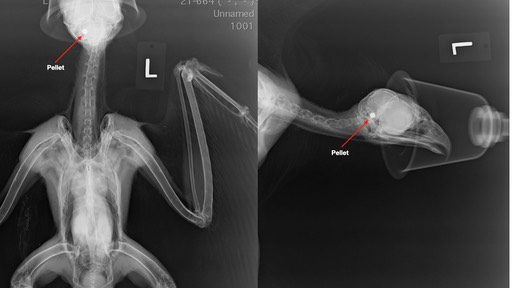

Gunshot Red-tailed Hawk 21-664

A hawk was found near College Place, WA unable to fly. It has a significant head tilt due to a head injury. Radiographs revealed the hawk had been shot. We will have to wait and see if the hawk can recover with supportive care.